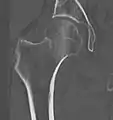

Subcapital fracture in a 92-year-old woman